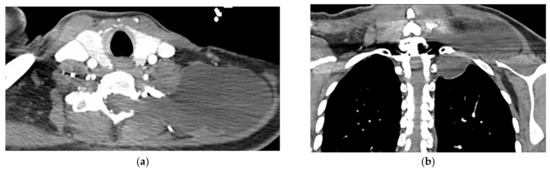

Tuberculosis spondylodiskitis has a more gradual and chronic clinical course, which leads to multi-level involvement and paravertebral cold abscess formation with well-circumscribed thin wall. Subligamentous spread of infection to adjacent vertebral levels, relative preservation of intervertebral disk, and kyphotic angulation (gibbous deformity) are other imaging findings. CT scan is more sensitive in delineating calcification within paravertebral cold abscess, end plate erosion, and bony fragment visualization (Figure 13) [39,42].

Figure 13.

A 65-year-old man with fever, weight loss, and night sweeting. The non-contrast-enhanced CT (bone window) in axial plane (a) shows paraspinal soft tissue mass with erosion of right lateral aspect of adjacent vertebral body. Sagittal T2W image of another patient with the same pathology (b) shows hypersignal intensity within T8-T9 vertebral bodies with also intervertebral disc destruction and narrowing of spinal canal pushing the spinal cord posteriorly. Axial T1WFS + C (c) identified the enhancing paraspinal mass with peripheral rim enhancement (arrow) in its left posteromedial side, which is suggestive of abscess formation. Culture of aspirated pus under guide of CT was compatible with tuberculosis infection.